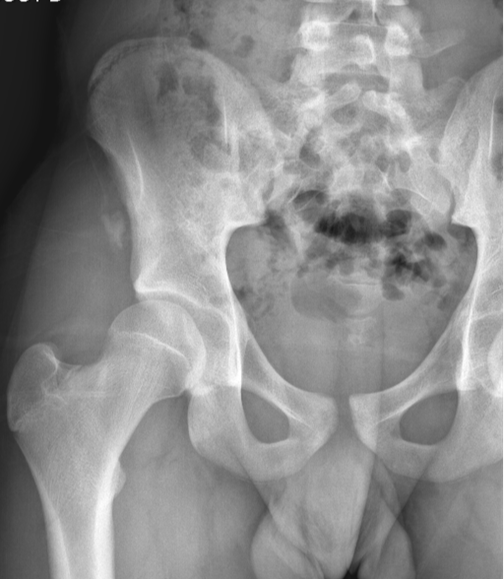

Standard pelvic radiography revealed a displaced bony fragment at the right AIIS. CT scan confirmed the avulsion fracture without intra-articular involvement or adjacent soft tissue injury.

Figure 1. Initial radiograph of the right hip: epiphyseal separation of the anterior inferior iliac spine.